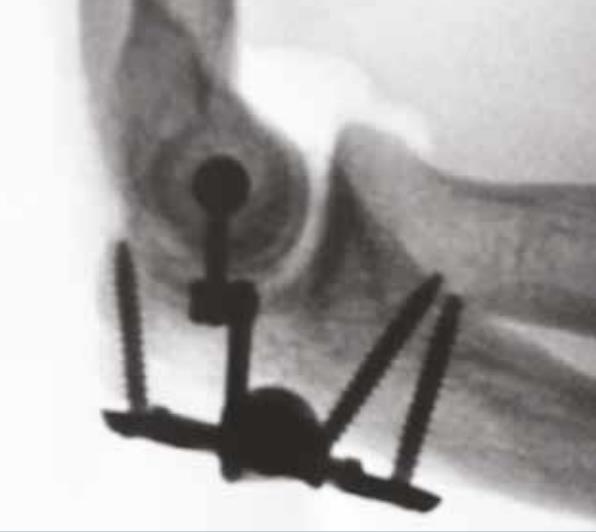

• Inserting the axis pin

• adjust the Distal Connecting Rod to allow the selected Axis Pin to be inserted through the eyelet of the Proximal Connecting Rod and into the humerus

• Locking the axis pin

• use the PROTEAN Pliers to stabilize the Proximal Connecting Rod while fully tightening the Axis Pin using the T-10 Driver

• Elbow reduction

• anatomically reduce the elbow joint

• Locking the construct

• using the T-10 Driver and the Counter Torque Tool, lock the reduction by first tightening the Proximal Locking Screw and then the Distal Locking Screw

• Final fluoroscopic confirmation

• confirm that the reduction is maintained through the full ROM using fluoroscopic imaging